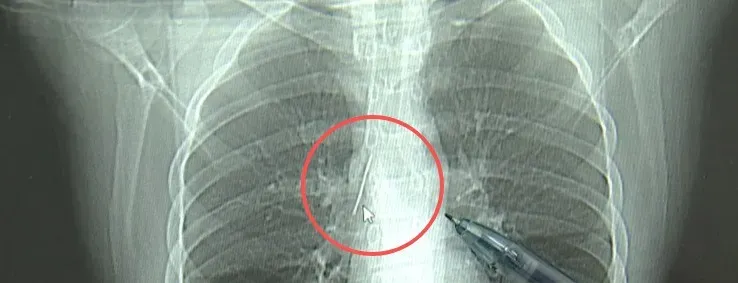

胸片结果显示:

胸腔内有一处金属高密度影,

形态细长,像一根针。

进一步的CT检查确认,异物是一枚金属针,斜插在肺组织内,位置十分凶险。